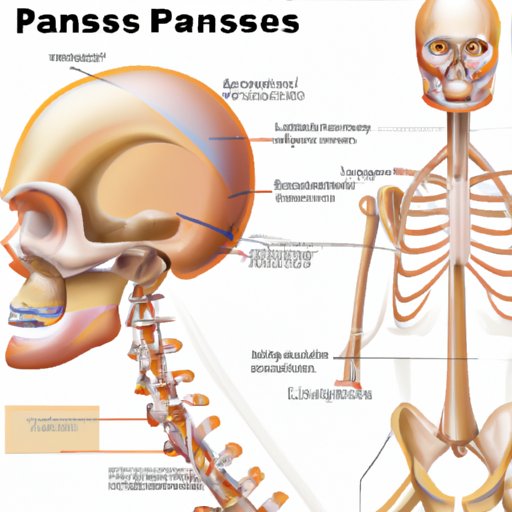

The Only Bone in the Human Body Without Paranasal Sinuses: A Unique Phenomenon

In this article, we explore the fascinating anatomy of the only bone in the human body without paranasal sinuses. This bone stands out among its counterparts, and its unique characteristics provide useful insights to medical research.